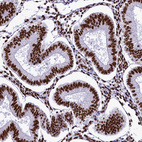

Immunohistochemical staining of human endometrium shows strong nuclear positivity in glandular cells.